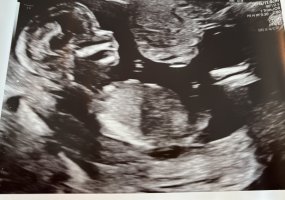

Hei! Noen som får til å se kjønnet på bildene? :shy: Jordmor var så usikker, så fikk ikke vite noe. I følge jordmor var jeg 14+2 på bildene.